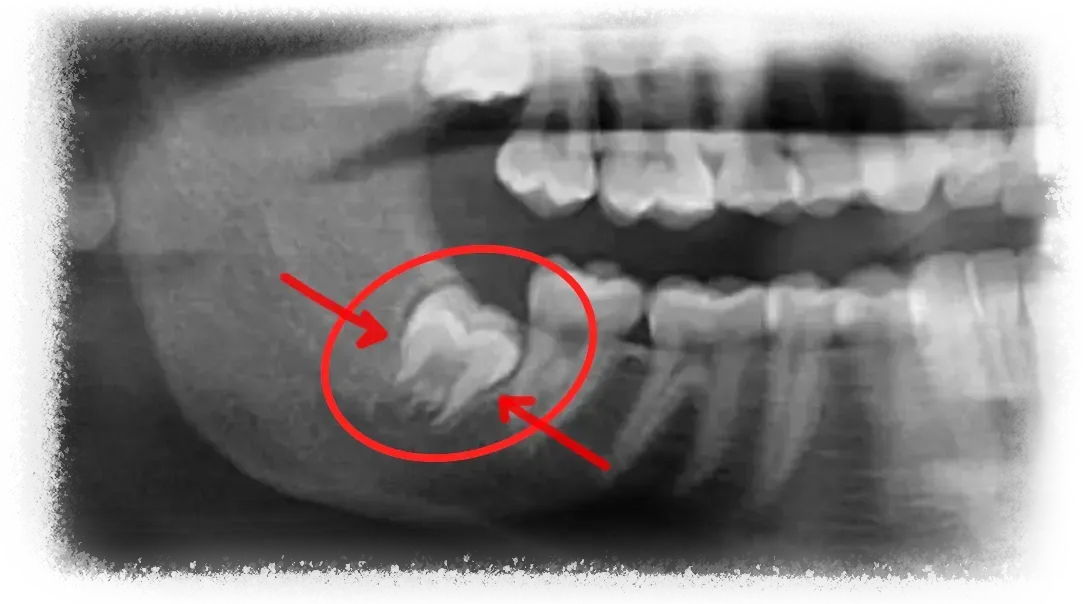

In many situations, yes. A large number of third molar extractions are referred simply because the process of evaluating case difficulty and planning the surgery isn't always clearly taught.